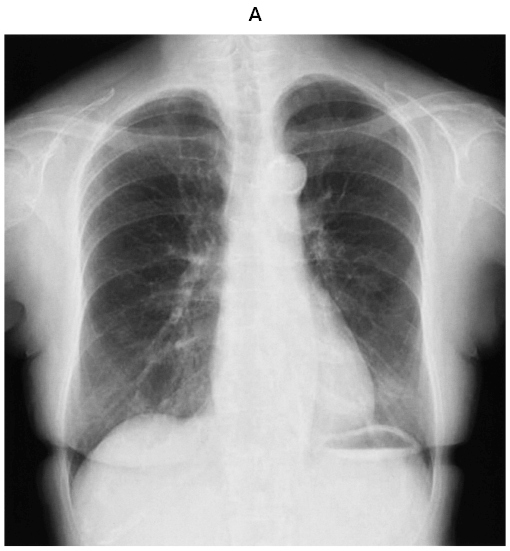

輝い 胸部X線画像診断アトラス 疾患が読める! | 江口研二 吉澤靖之, 医学一般